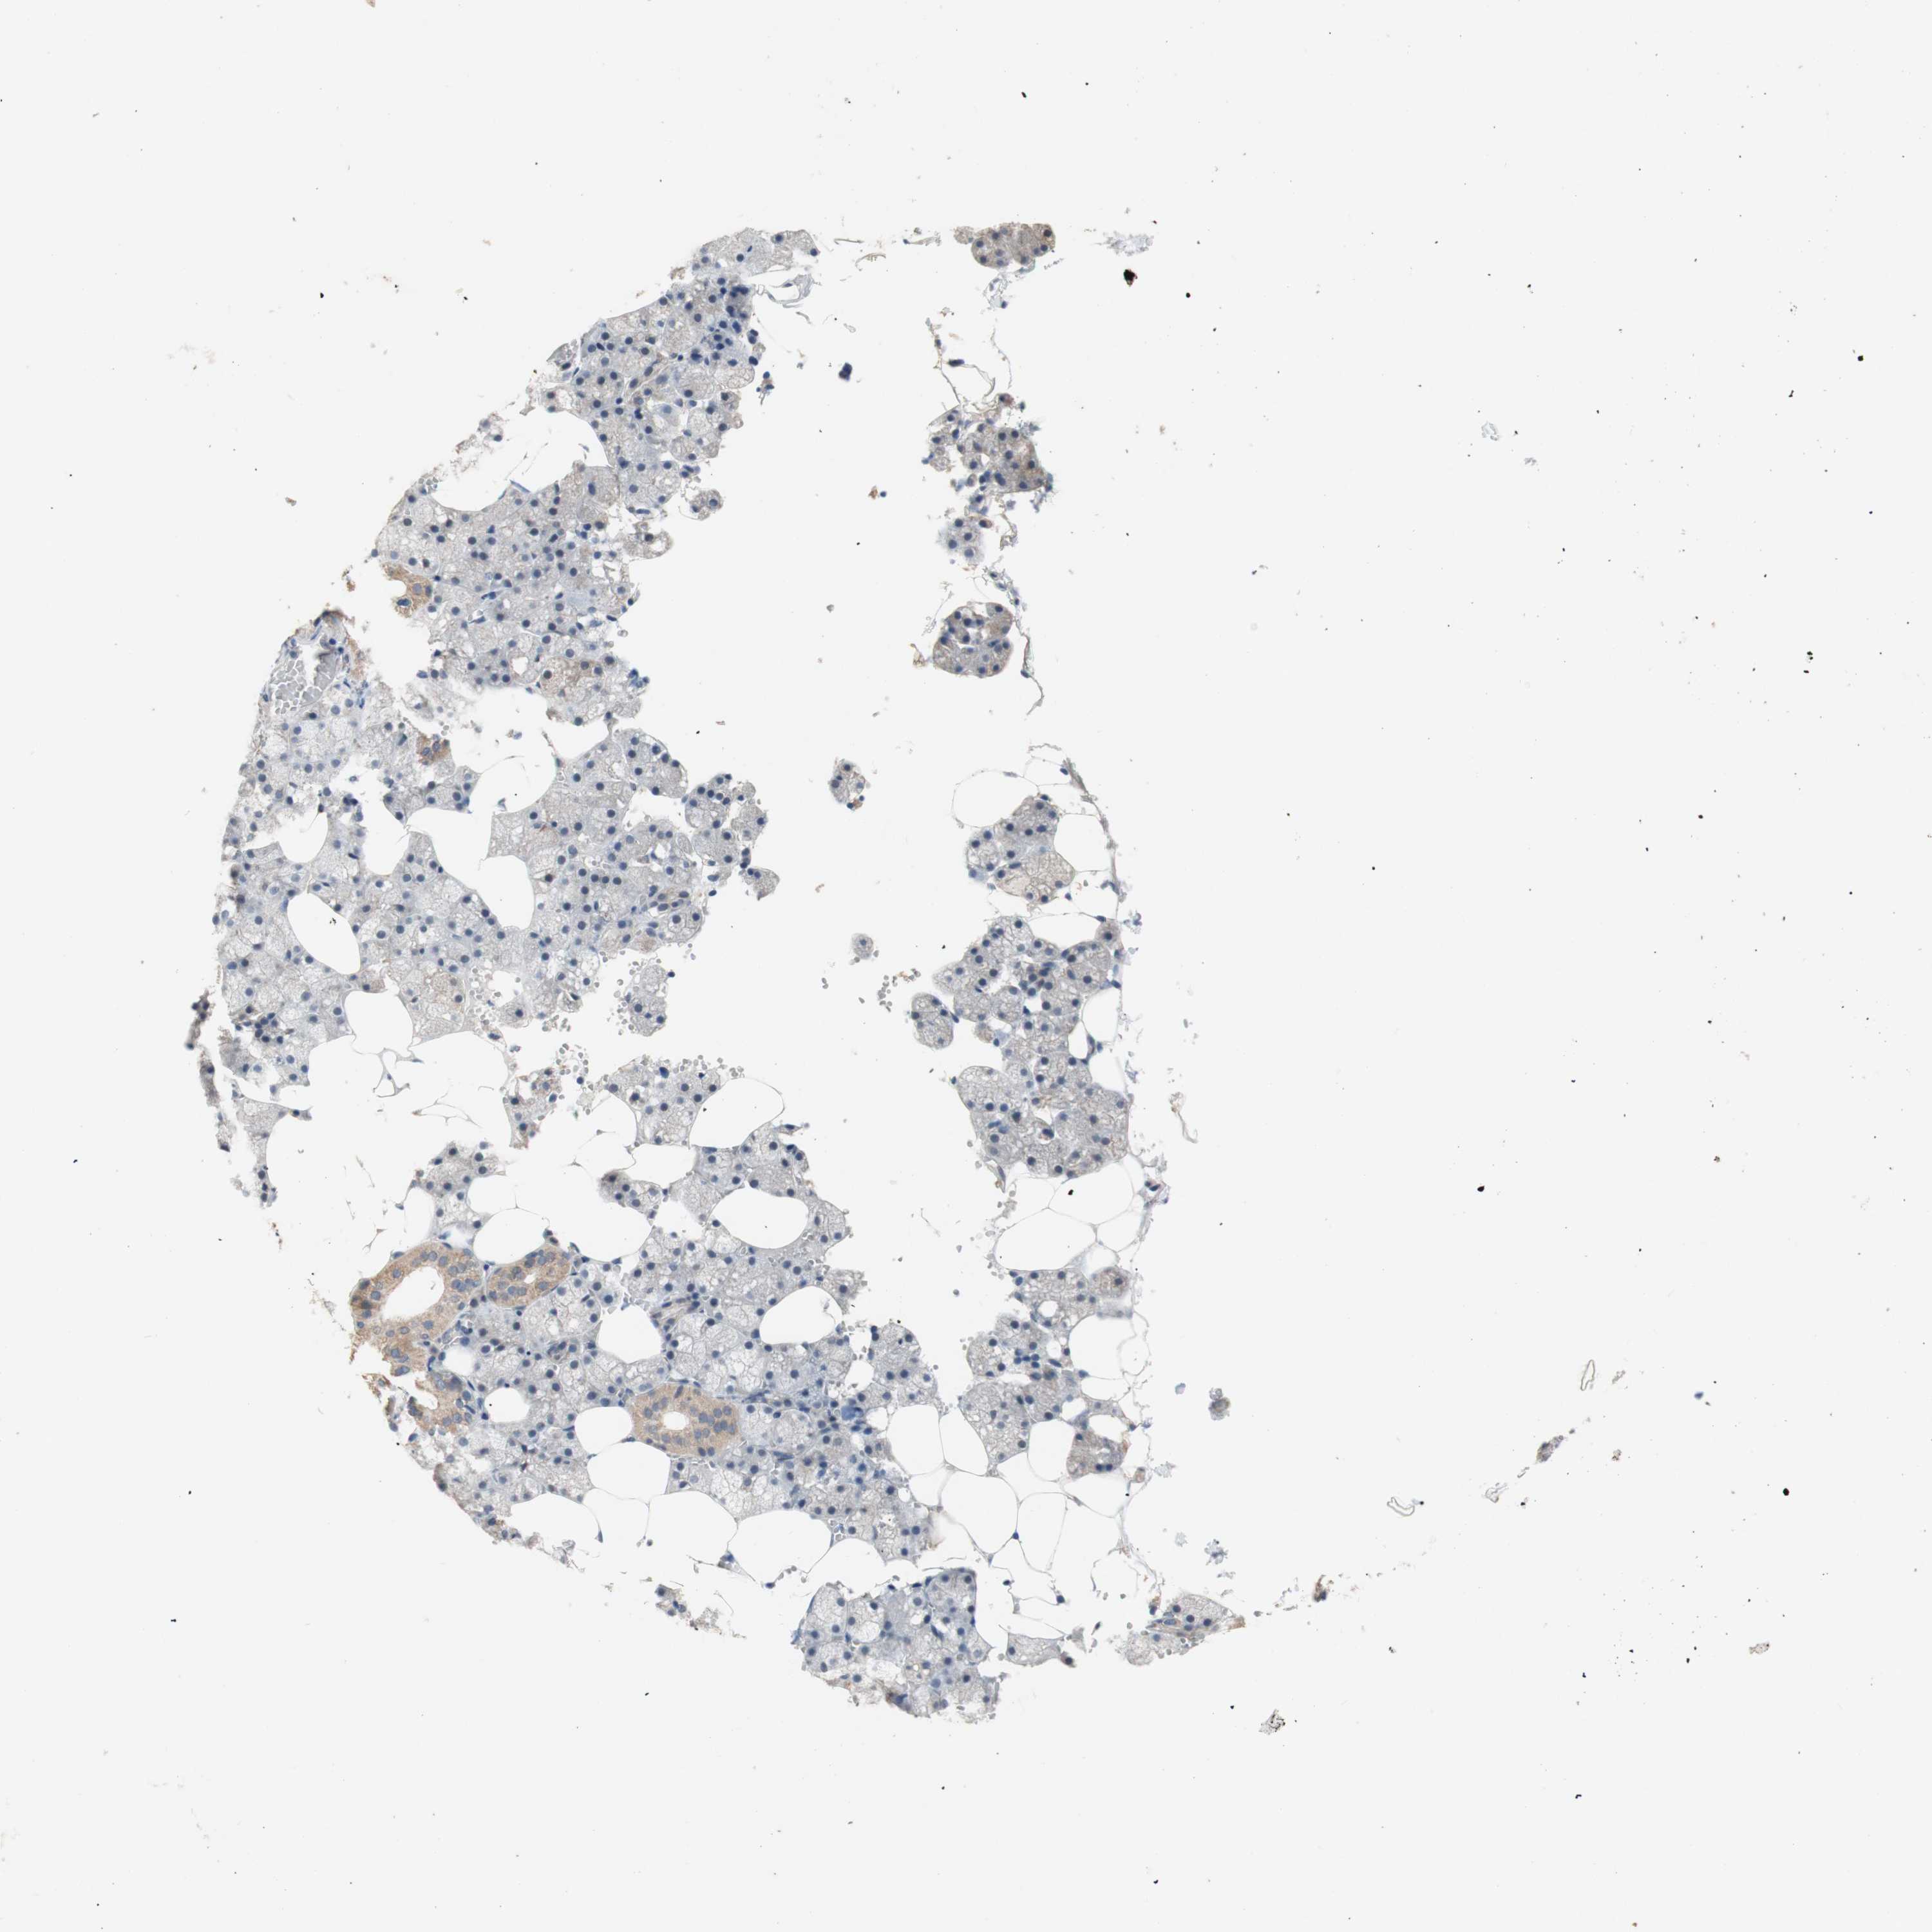

SALIVARY GLAND - Antibody stainingi

Antibody staining in the annotated cell types in the current human tissue is reported as not detected, low, medium, or high, based on conventional immunohistochemistry profiling in selected tissues. This score is based on the combination of the staining intensity and fraction of stained cells.

Each image is clickable and will lead to virtual microscopy that enables deeper exploration of all samples and also displays staining intensity scores, fraction scores and subcellular localization as well as patient and tissue information for each sample.

Antibody HPA014193Antibody CAB009517

Glandular cells LowNot detected